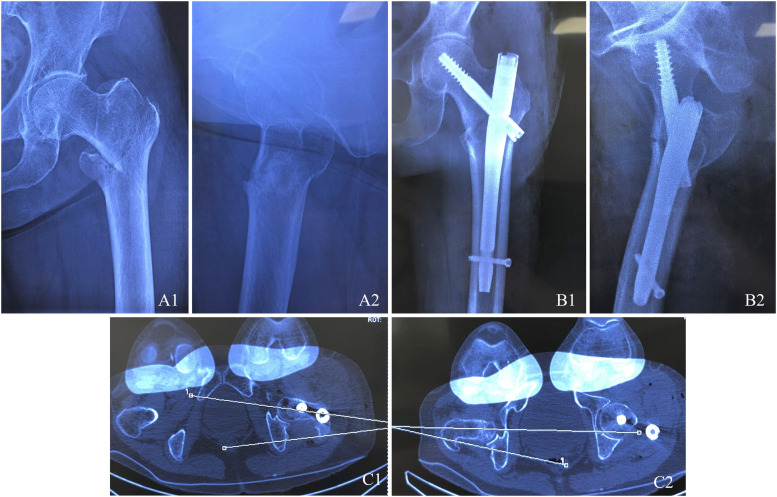

目的:利用三维(3D) CT成像定量分析股骨粗隆间骨折髓内钉内固定后的旋转位移,分析相关危险因素,并评价其临床意义。方法:本研究纳入了2019年至2023年期间接受股骨粗隆间骨折髓内钉固定治疗的252例患者。所有参与者术后接受三维计算机断层扫描(3D CT),随访至少1年。术后对患侧股骨前倾进行定量评估。分析其与潜在危险因素的相关性,包括年龄、性别、体重指数(BMI)、美国麻醉学会(ASA)分级、甲长、内固定类型、复位质量、AO基金会/骨科创伤协会(AO/OTA)骨折分型、有无内侧皮质缺损、骨矿物质密度(T-score)、Singh指数、相对外侧壁厚度(rLWT)、尖端距离(TAD)、颈轴角、以及骨折分类。通过随访评估前倾的差异对长期临床结果的影响,包括视觉模拟量表(VAS)疼痛评分和Harris髋关节评分(HHS)。结果:筛选排除标准后,共有210例患者入组研究:33例(15.7%)患者前倾差异超过15°;15°以下177例(84.3%)。在版本偏差为2.5的亚组中,rLWT和骨折分类被认为是导致旋转位移超过15°的主要因素。在1年的随访中,旋转位移较小的患者表现出更好的功能恢复,这可以通过改善的视觉模拟量表(VAS)疼痛评分和Harris髋关节评分(HHS)来反映。多元线性回归分析显示,髓内钉固定后rLWT与骨折碎片旋转位移有显著相关性。结论:股骨粗隆间骨折髓内钉固定后常发生骨旋转移位。rLWT与这些并发症密切相关。因此,对手术技术的细致关注对于减少并发症和优化结果至关重要。

Methods: This study enrolled a cohort of 252 patients who underwent intramedullary nail fixation for intertrochanteric femoral fractures between 2019 and 2023. All participants underwent postoperative three-dimensional computed tomography (3D CT) and were followed for a minimum of 1 year. Postoperative femoral anteversion on the affected side was quantitatively assessed. An analysis was conducted to evaluate its correlation with potential risk factors, including age, sex, body mass index (BMI), American Society of Anesthesiologists (ASA) classification, nail length, type of internal fixation, reduction quality, AO Foundation/Orthopaedic Trauma Association (AO/OTA) fracture classification, presence of medial cortical defect, bone mineral density (T-score), Singh's index, relative lateral wall thickness (rLWT), tip-apex distance (TAD), neck-shaft angle, and fracture classification. The impact of differences in anteversion on long-term clinical outcomes, including Visual Analog Scale (VAS) pain scores and Harris Hip Scores (HHS), was assessed through follow-up evaluations.

Results: After screening for exclusion criteria, a total of 210 patients were enrolled in the study: 33 patients (15.7%) exhibited differences in anteversion exceeding 15°; 177 patients (84.3%) were under 15°. In the subgroup with version deviations <15°, precise anatomical restoration (anteversion ≤5°) was achieved in 138 cases (77.9%), consistent with optimal biomechanical reconstruction targets; functionally compensated malrotation (5° < anteversion <15°) occurred in 39 patients (22.1%), within the tolerance range for gait adaptation without clinical impairment. Single-nail fixation, medial cortical defects, T-score >2.5, rLWT and fracture classification were identified as the primary factors contributing to rotational displacement exceeding 15°. At the 1-year follow-up, patients with smaller rotational displacement demonstrated better functional recovery, as reflected by improved Visual Analog Scale (VAS) pain scores and Harris Hip Scores (HHS).The multivariate linear regression analysis demonstrated that the rLWT showed significant correlation with rotational displacement of fracture fragments after intramedullary nail fixation.